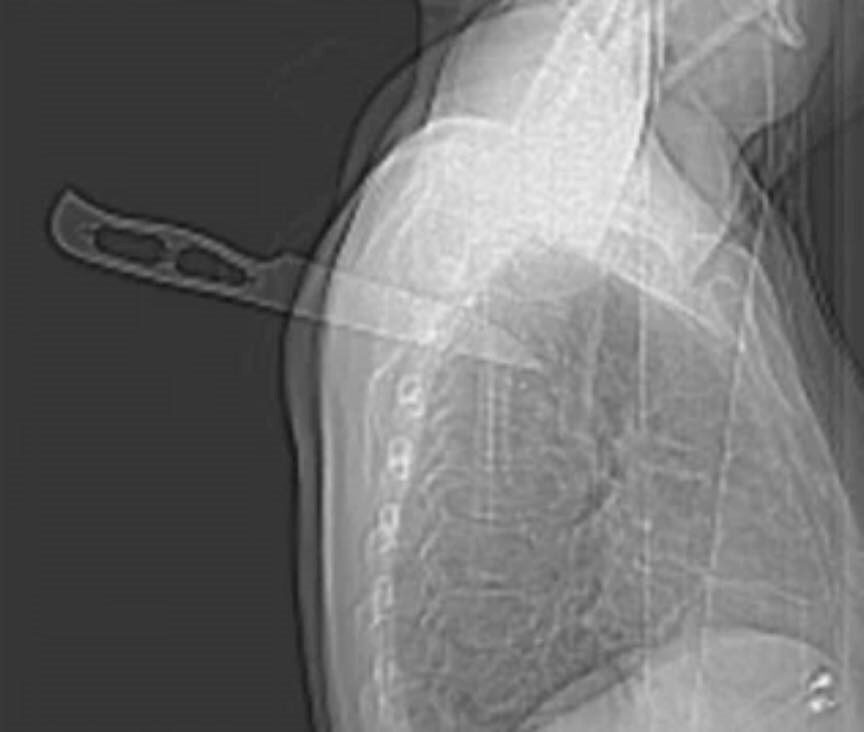

นพ.สมรส พงศ์ละไม ออกมาโพสต์ข้อความผ่าน Somros MD Phonglamai จนกลายเป็นกระแสไวรัลที่ชาวเน็ตต่างฮือฮากันยกใหญ่ ระบุ "คนไข้โดนมีดแทงข้างหลัง ทะลุเข้าไป 9 เซนติเมตร ที่ตำแหน่งกระดูกสันหลังระดับอก (T3-T4) ปกติคนไข้กลุ่มนี้จะบาดเจ็บสาหัส พิการ เดินไม่ได้ แต่คนนี้ปาฏิหารย์ ไม่ตาย และสามารถฟื้นฟูกลับมาเป็นปกติ ในเวลา 10 เดือน เอ๊ย 6 เดือน"

โดยผู้ป่วยชายอายุ 50 ปี เข้ารับการรักษาฉุกเฉินเนื่องจากบาดแผลถูกแทงลึกถึงทรวงอก 3 - 4 แผล เนื่องจากมีดแทงเข้าไปในช่องไขสันหลังและยังค้างอยู่ในกระดูกสันหลัง ผู้ป่วยนอนคว่ำและมีดอยู่ในตำแหน่งที่ปลอดภัย เขามีสติและตื่นตัว สัญญาณชีพของเขาเป็นปกติ

การตรวจระบบประสาทของผู้ป่วยเป็นปกติ มีดถูกถอนออกในห้องผ่าตัดภายใต้การดมยาสลบโดยไม่มีเลือดออกหรือน้ำไขสันหลังรั่ว หลังจากถอนการตรวจระบบประสาทเป็นปกติและควบคุมการถ่ายภาพด้วยคลื่นแม่เหล็กไฟฟ้าไม่พบความผิดปกติใด ๆ ซึ่งพบว่ามีปลายใบมีดยาว 9 ซม. อยู่ภายใน และมีบาดแผลขนาด 2 ซม.